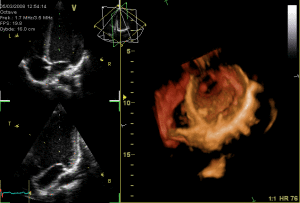

Ecocardiografia 3D riduce rischi durante intervento alle valvole cardiache

Immagine ecocardiografia 3D

Ridotte del 10 % le complicanze degli interventi alle valvole cardiache attraverso un’ecocardiografia tridimensionale che guida la mano del chirurgo senza bisogno di un intervento a cuore aperto. Gli ultimi dati sul trattamento innovativo, che e’ gia disponibile presso alcuni centri in Italia, sono stati presentati nell’ambito del trentesimo Congresso della Societa’ italiana di cardiologia invasiva dal direttore della Divisione di cardiologia invasiva dell’istituto Montevergine di Mercogliano, Paolo Rubino.

Cliccare sull’immagine per vedere il movimento

L’ecocardiografia 3D, permettendo di avere una valutazione piu’ accurata delle valvole cardiache senza il bisogno di un intervento al torace, consente pertanto un piu’ corretto posizionamento della valvola con una significativa riduzione di almeno il 10 % delle complicanze, come ad esempio lo spostamento della protesi. ‘In Italia gli interventi su persone che hanno la malattia delle valvole sono circa 10mila l’anno – ha spiegato Paolo Rubino – se fino a ieri il paziente veniva trattato con la chirurgia tradizionale oggi e’ possibile sostituire le valvole cardiache senza aprire il torace nei pazienti ad alto rischio chirurgico’.